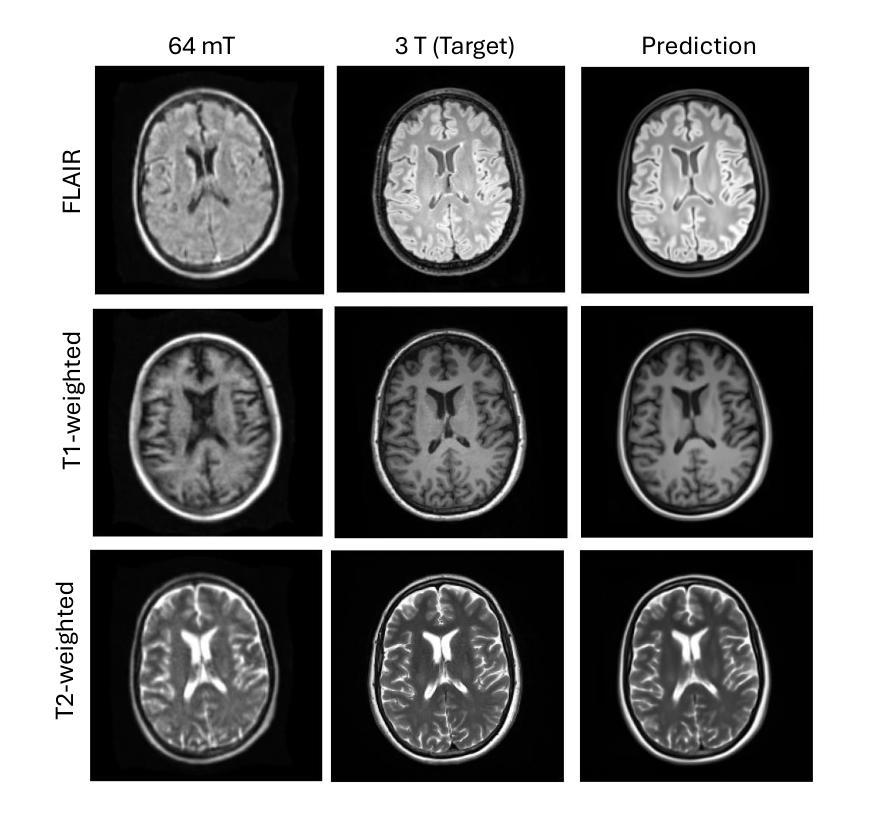

Augment to Augment: Diverse Augmentations Enable Competitive Ultra-Low-Field MRI Enhancement

Authors:Felix F Zimmermann

Ultra-low-field (ULF) MRI promises broader accessibility but suffers from low signal-to-noise ratio (SNR), reduced spatial resolution, and contrasts that deviate from high-field standards. Image-to-image translation can map ULF images to a high-field appearance, yet efficacy is limited by scarce paired training data. Working within the ULF-EnC challenge constraints (50 paired 3D volumes; no external data), we study how task-adapted data augmentations impact a standard deep model for ULF image enhancement. We show that strong, diverse augmentations, including auxiliary tasks on high-field data, substantially improve fidelity. Our submission ranked third by brain-masked SSIM on the public validation leaderboard and fourth by the official score on the final test leaderboard. Code is available at https://github.com/fzimmermann89/low-field-enhancement.

超低场(ULF)MRI虽然为更广泛的可用性提供了潜力,但却存在信号噪声比(SNR)低、空间分辨率降低以及偏离高场标准的对比度等问题。图像到图像的翻译可以将ULF图像映射到高场外观,但其有效性受限于稀缺的配对训练数据。在ULF-EnC挑战的限制条件下(50对3D体积;无外部数据),我们研究了任务适应性数据增强如何影响用于ULF图像增强的标准深度模型。我们表明,包括在高场数据上的辅助任务在内的强大且多样化的增强措施,可以大大提高保真度。我们的提交在公共验证排行榜上以脑掩膜SSIM排名第三,在最终测试排行榜上以官方评分排名第四。代码可在https://github.comcom/fzimmermann89/low-field-enhancement获取。

超低频MRI虽有望提高普及性,但存在信号噪声比低、空间分辨率降低及对比度偏离高频标准等问题。图像到图像的转换可将低频图像映射到高频外观,但其有效性受限于配对训练数据的稀缺性。在ULF-EnC挑战的限制条件下(50对三维体积数据,无外部数据),我们研究了任务适应性数据增强对低频图像增强标准深度模型的影响。研究显示,包括高频数据辅助任务在内的强大、多样化的数据增强显著提高了保真度。我们的提交在公开验证排行榜上以脑掩膜SSIM排名第三,在最终测试排行榜上排名第四。代码可在链接处获取。